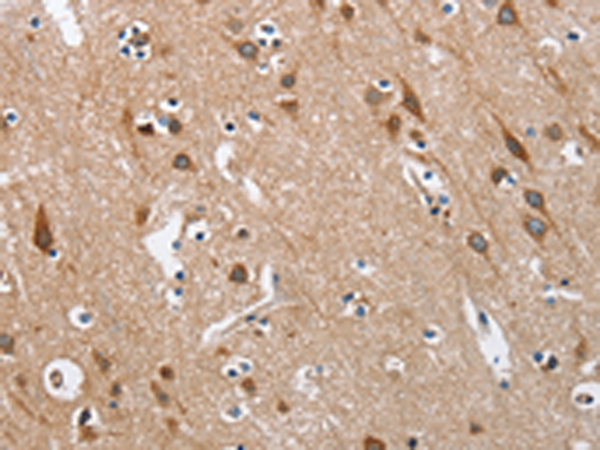

分类: 科研抗体货号: P07389别名: MUM1; LSIRF; SHEP8; NF-EM5应用: IHC反应种属: Human, Mouse